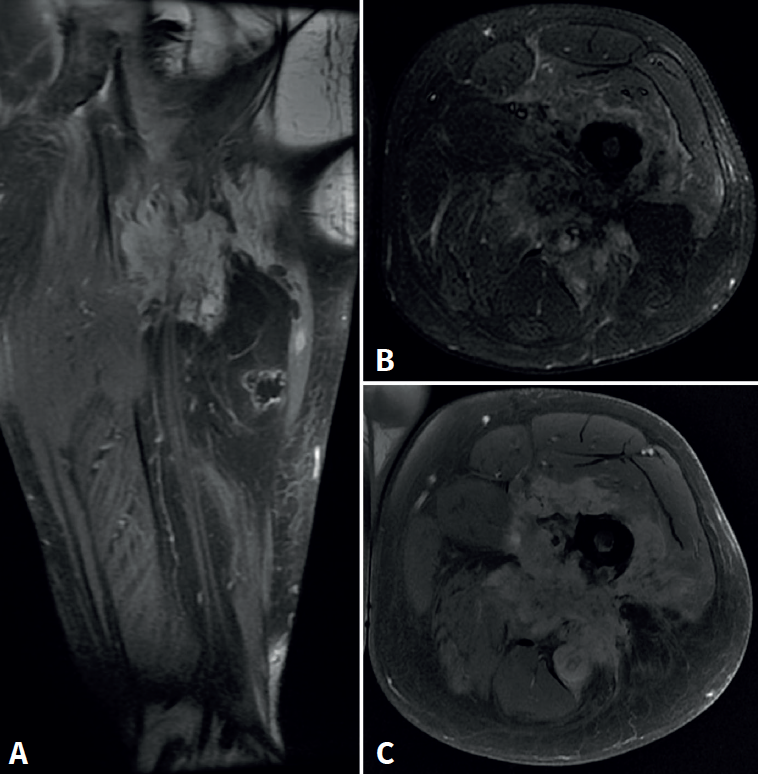

Cincuenta días tras el accidente se realizó fusión lumbar instrumentada L4-L5 con inserción de dispositivo intersomático por vía transforaminal derecha. En el segundo día postoperatorio presentó empeoramiento del dolor, objetivándose en la tomografía computarizada (Figura 2) malposición del tornillo L5 izquierdo que invadía el canal. Se reintervino a los 5 días corrigiendo el trayecto del tornillo. Sin embargo, persistió el dolor. La revaluación del caso, sumada a los hallazgos de EMG, motivó estudios complementarios de pierna y trayecto ciático (Figuras 3 y 4), detectándose una masa tumoral en el fémur izquierdo compatible con sarcoma fusocelular.

La literatura recoge múltiples causas de ciática extravertebral. Koh et al. describen neuropatías del espacio subglúteo –incluyendo atrapamientos del nervio ciático, cluneal o pudendo– como responsables de dolor ciático crónico, clínicamente indistinguibles de una radiculopatía(2). Otros autores han informado casos de pseudociática secundaria a lesiones musculares: un hematoma en el músculo gemelo inferior(4) o un desgarro del bíceps femoral en contacto con el nervio ciático(6). También se han reportado tumores pélvicos y de la extremidad proximal, como sarcomas que debutan con dolor ciático sin otros síntomas específicos(3,5). Nuestro caso comparte elementos con estas publicaciones: la falta de respuesta a la cirugía lumbar, los hallazgos electromiográficos posganglionares y la persistencia del dolor obligaron a replantear el diagnóstico. Finalmente, la identificación de un sarcoma fusocelular femoral como causa del dolor refuerza la necesidad de un enfoque diagnóstico integral.